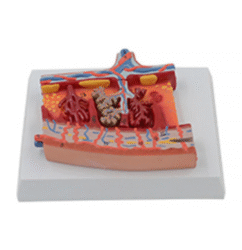

ATL-103 MULTI-FUNCTIONAL INTRA-MUSCULAR INJECTION TRAINING PAD SOFT

The model consists of skin, subcutaneous tissue and muscle layer. Can be used for intradermic injection,hypodermic injection and intramuscular injection. A wearable design makes it convenient for training.Injection liquid can be injected into it, squeeze the pad after use.

Packing: 32pcs/carton, 62x29x29cm, 16kgs